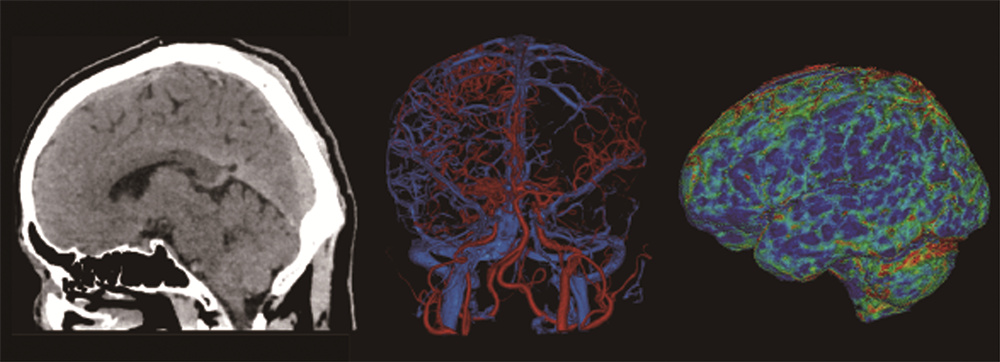

联影640层CT是中国CT届的“天花板”,集当今CT领域的顶尖科技于一身,将各项临床应用发挥到极致,为患者带来精准、舒适、安全的CT检查新体验。建立了心血管、神经、肿瘤、呼吸系统、泌尿系统及骨科专业等疾病的成像和低剂量筛查领域全新标准,真正实现全方位成像,结合AI人工智能技术,提高疾病诊断率。

联影640层CT采用宽体采集,一次检查即可获得全脑平扫图像、动静脉造影图像和灌注图像,不仅可应用于急诊缺血性脑卒中的影像评估,还可助力脑血管畸形、脑动脉瘤等其他脑血管病的结构和功能评估。